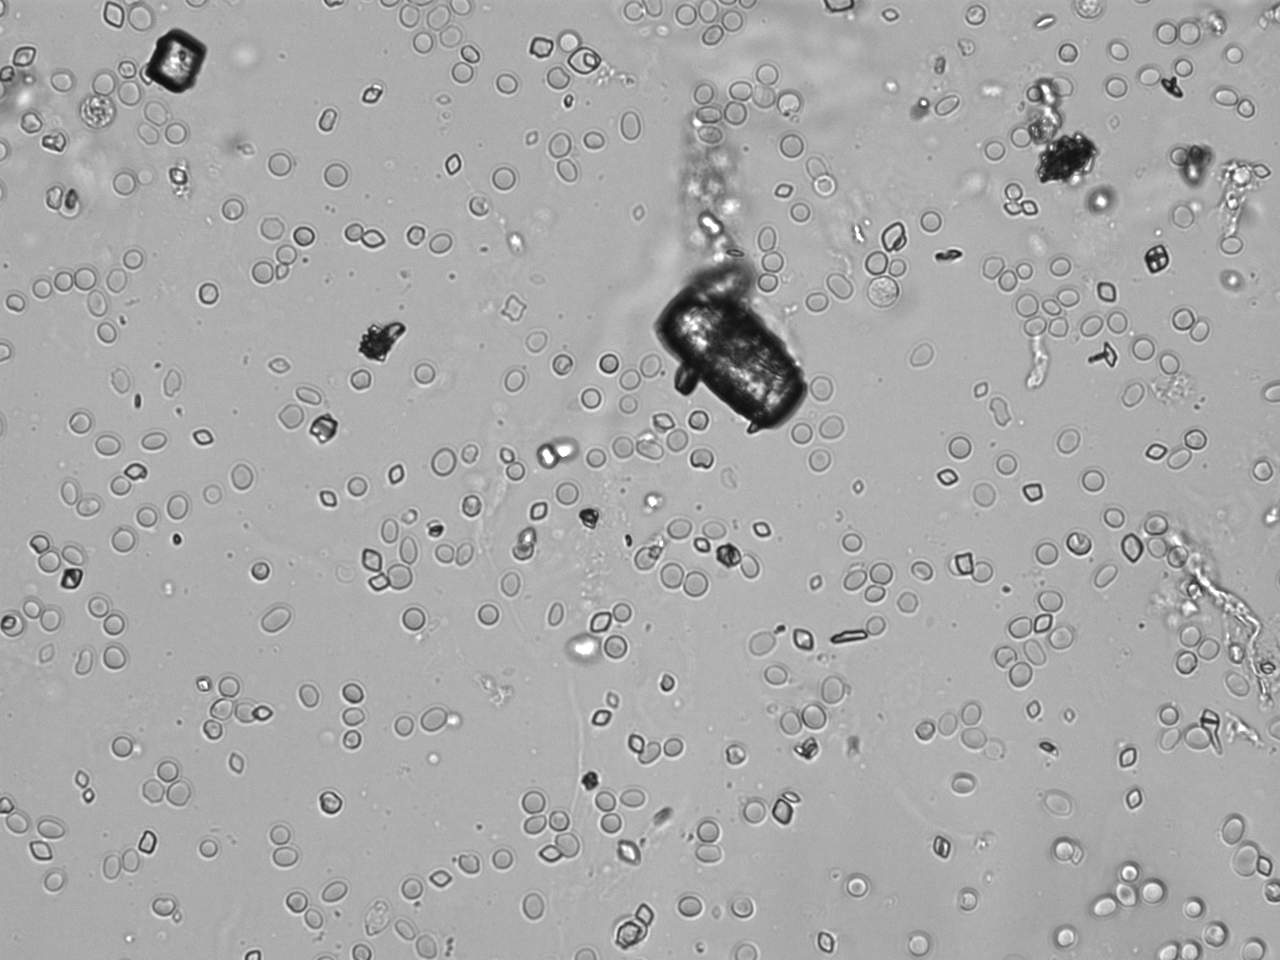

Urin-Feature: Harnskristalle_Rhomboid